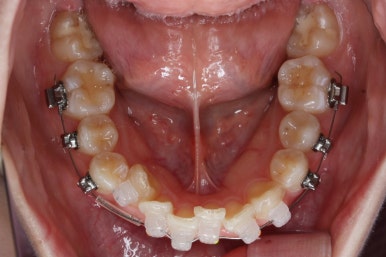

위 사진은 연산동교정치과 처음 내원하셨을 때의 입안 모습입니다. 몇 가지 모습이 관찰됩니다.

치아가 삐뚤삐뚤합니다.

위~아래 앞니가 많이 겹쳐서 아랫니가 많이 모이지 않는 "과개교합" 입니다.

앞니가 앞으로 뻐뜨러져 있습니다.